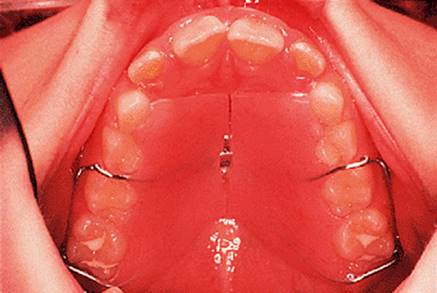

Before discussing functional appliances in detail, Fig. 18.1 gives an overview of this type of functional appliance in clinical use. This patient has a Class II division 1 malocclusion of the type for which functional appliances are very suitable, and for which they have been used for many years.

There are a number of important features to note which will be discussed further later in the chapter. First, the patient is still growing and the signs are that her pattern of facial growth is likely to be favourable. Although the skeletal pattern is Class II, the vertical relationships are close to average and the direction of mandibular growth is likely to be a mild forward rotation (see Chapter 4) which is favourable to the correction of a Class II malocclusion. Second, the soft tissue morphology is favourable despite the lips being incompetent, with the lower lip resting behind the upper incisors. The lower lip line is above the level of the upper incisal edges, and after the overjet has been reduced the lower lip will rest labially to the upper incisors, so helping to resist any tendency for relapse of the overjet. Third, the arches are well aligned — functional appliances have no mechanism for treating irregularities of alignment of the teeth.

The appliance holds the mandible in a forward postured position, in this case with the incisors edge to edge (Fig. 18.1(f)). The facial musculature is thus stretched, and applies a posterior force to the upper arch and an anterior force to the lower arch. The lower incisors have acrylic capping to prevent excessive labial tilting of the lower incisors, and this also serves as a bite-plane to reduce the overbite (Chapter 10). The appliance must be worn for at least 14–16 hours each day, but once the overjet has been reduced fully the amount of daily wear can gradually be reduced to sleeping hours only. The patient should continue to wear the appliance overnight in this way as a retainer, at least until the period of rapid pubertal growth is complete. Figures 18.1(g) and 18.1(h) show the dental and facial changes which occurred during treatment.

Fig. 18.1. (a) This 12-year-old girl had a skeletal II facial pattern and average facial proportions. The lips were incompetent with the lower lip lying below the upper incisors at rest. (b), (c) She had a Class II division 1 malocclusion with an overjet of 10 mm, the overbite was increased and complete, and the molar relationship was Class II on both sides. (d), (e) The upper and lower arches were well aligned. (f) A functional appliance (an activator) was fitted. (g) The corrected occlusion with Class I incisor and molar relationships. (h) The patient's facial profile at the end of treatment.